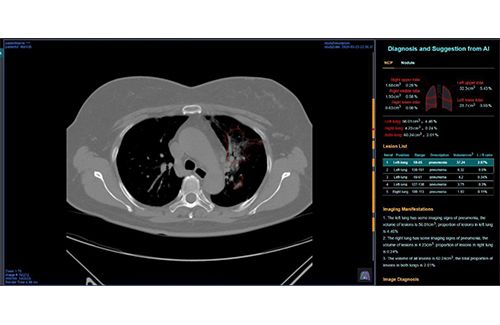

Dijelaskan Ahmad, dengan memanfaatkan teknologi AI dari Huawei, pihaknya dapat secara langsung mengetahui kondisi paru-paru pasien dan munculnya area pelukaan pada organ tersebut yang menjadi beberapa penanda adanya gejala akibat infeksi Covid-19, sebelum dilakukan konfirmasi oleh dokter spesialis radiologi.

gambaran Pneumonia sejak di tahap awal. Melalui alat buatan Huawei ini, dalam kisaran waktu sekira 30 detik kami bisa memperoleh indikasi apakah pasien terinfeksi COVID-19 atau tidak. Ketika didapatkan gambaran normal, maka akan muncul ikon warna hijau. Namun ketika didapatkan gambaran infiltrat (ciri khas pneumonia), ikon warna merah akan muncul. Dengan kata lain, pasien tersebut terindikasi terinfeksi virus,” jelasnya. Menurutnya, solusi ini sangat bermanfaat bagi RSPP untuk melakukan percepatan treatment lanjutannya. Dalam aplikasi AI Huawei juga, ketika ditemukan gambaran akibat infeksi virus, akan langsung diketahui volumenya dan segmen-segmen wilayah parunya. Hal ini akan memberikan referensi tambahan bagi radiolog dalam melakukan ekspertisnya. Jika aplikasi ini diberikan akses ke klinisi pengirim akan sangat membantu dalam percepatan tindakan lanjutan untuk mereka, sembari menunggu hasil ekspertis radiologis. Ditambahkan Ahmad, tingkat akurasi dengan menggunakan teknologi AI Huawei juga sangat tinggi. Dari 50 data pasien yang diperiksa, disandingkan dengan ekpertis radiologis, tingkat akurasinya mencapai 93%. Menurutnya, pihaknya optimistis, dengan makin banyaknya data-data yang akan bertambah dan dianalisis melalui teknologi AI dari Huawei, maka hasil ke depannya akan makin bertambah akurat. Sementara itu Vice President Public Affairs and Communications Huawei Indonesia,Ken Qijian mengatakan, kontribusi ini adalah bagian dari tanggung jawab sosial korporasi Huawei untuk dunia, termasuk Indonesia. "Kami berharap, dengan menyinergikan kemampuan teknologi terdepan dari Huawei dengan kepakaran-kepakaran di bidang lain, seperti dunia kesehatan dan juga bidang-bidang lainnya, dunia akan segera berhasil menuntaskan persoalan COVID-19. Mari bahu-membahu dan bersatu untuk mengalahkan pandemi ini," tegasnya. (sg)

“Kami sangat terbantu dengan adanya teknologi AI dari Huawei ini. Solusi ini mampu mendeteksigambaran Pneumonia sejak di tahap awal. Melalui alat buatan Huawei ini, dalam kisaran waktu sekira 30 detik kami bisa memperoleh indikasi apakah pasien terinfeksi COVID-19 atau tidak. Ketika didapatkan gambaran normal, maka akan muncul ikon warna hijau. Namun ketika didapatkan gambaran infiltrat (ciri khas pneumonia), ikon warna merah akan muncul. Dengan kata lain, pasien tersebut terindikasi terinfeksi virus,” jelasnya. Menurutnya, solusi ini sangat bermanfaat bagi RSPP untuk melakukan percepatan treatment lanjutannya. Dalam aplikasi AI Huawei juga, ketika ditemukan gambaran akibat infeksi virus, akan langsung diketahui volumenya dan segmen-segmen wilayah parunya. Hal ini akan memberikan referensi tambahan bagi radiolog dalam melakukan ekspertisnya. Jika aplikasi ini diberikan akses ke klinisi pengirim akan sangat membantu dalam percepatan tindakan lanjutan untuk mereka, sembari menunggu hasil ekspertis radiologis. Ditambahkan Ahmad, tingkat akurasi dengan menggunakan teknologi AI Huawei juga sangat tinggi. Dari 50 data pasien yang diperiksa, disandingkan dengan ekpertis radiologis, tingkat akurasinya mencapai 93%. Menurutnya, pihaknya optimistis, dengan makin banyaknya data-data yang akan bertambah dan dianalisis melalui teknologi AI dari Huawei, maka hasil ke depannya akan makin bertambah akurat. Sementara itu Vice President Public Affairs and Communications Huawei Indonesia,Ken Qijian mengatakan, kontribusi ini adalah bagian dari tanggung jawab sosial korporasi Huawei untuk dunia, termasuk Indonesia. "Kami berharap, dengan menyinergikan kemampuan teknologi terdepan dari Huawei dengan kepakaran-kepakaran di bidang lain, seperti dunia kesehatan dan juga bidang-bidang lainnya, dunia akan segera berhasil menuntaskan persoalan COVID-19. Mari bahu-membahu dan bersatu untuk mengalahkan pandemi ini," tegasnya. (sg)